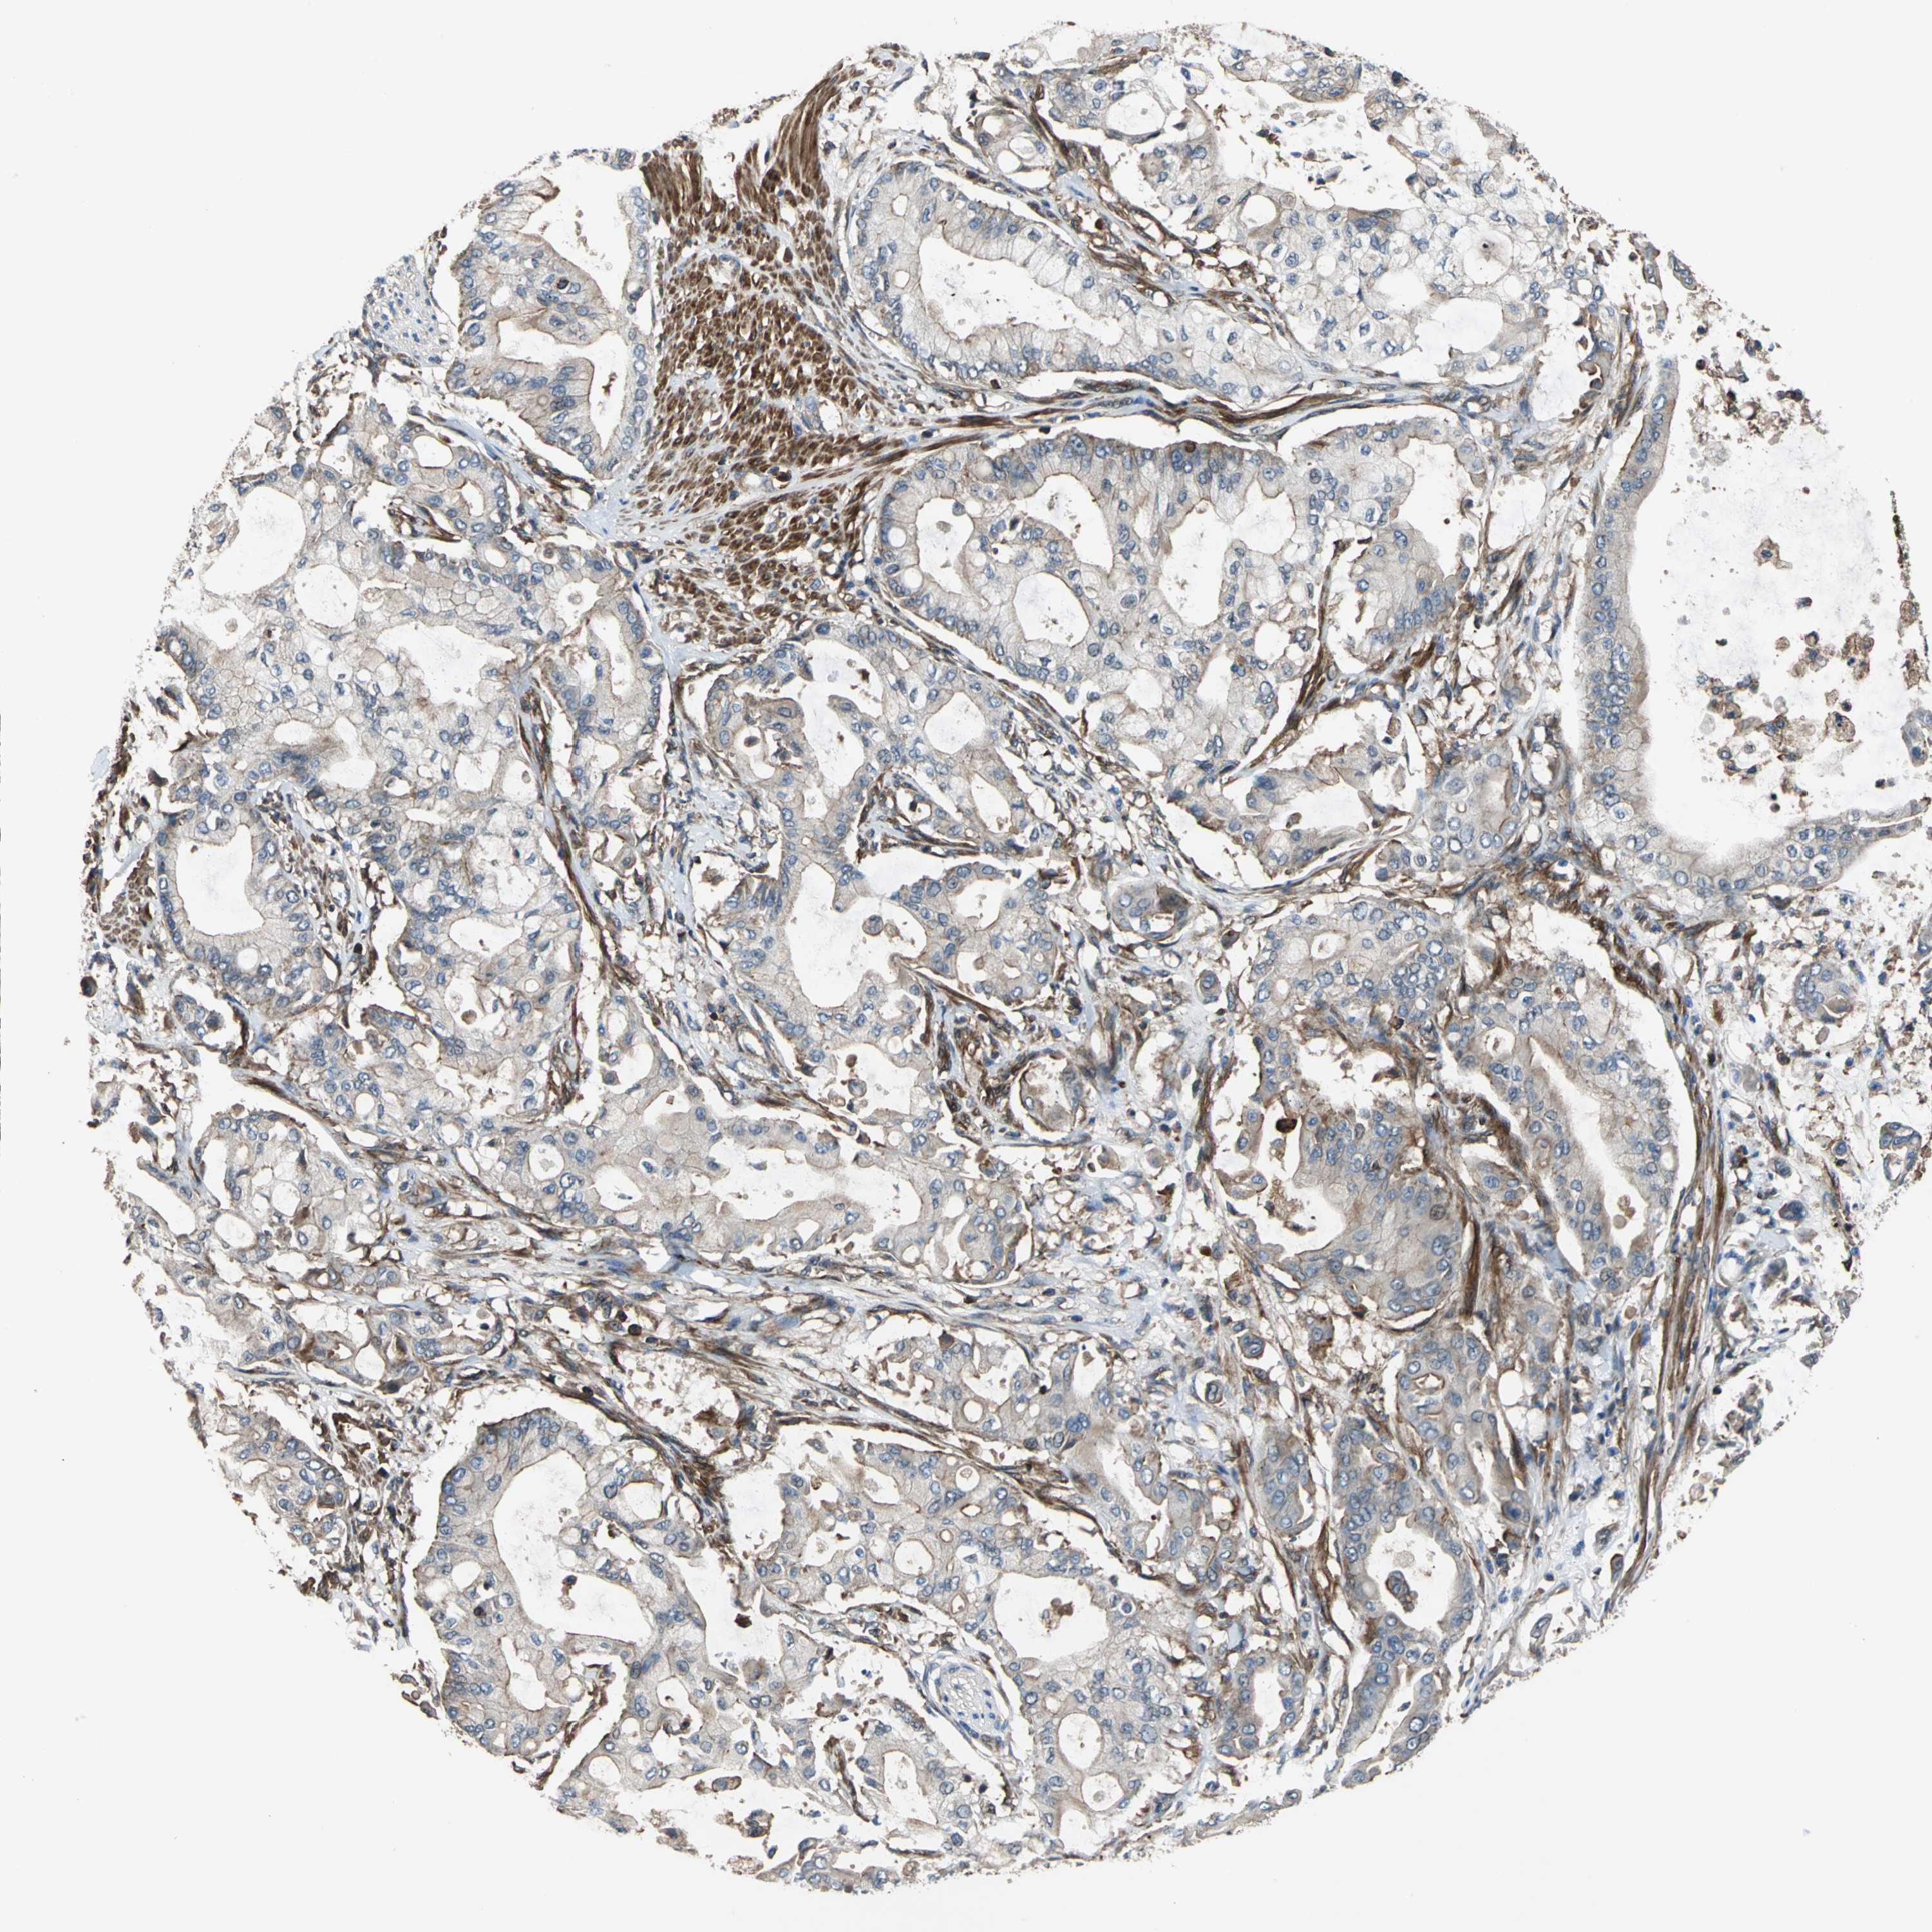

PANCREATIC CANCER - Protein expressioni

A mouse-over function shows sample information and annotation data. Click on an image to view it in a full screen mode. Samples can be filtered based on level of antibody staining by selecting one or several of the following categories: high, medium, low and not detected. The assay and annotation is described here.

Note that samples used for immunohistochemistry by the Human Protein Atlas do not correspond to samples in the TCGA dataset.

Antibody stainingi

Antibody staining in the annotated cell types in the current human tissue is reported as not detected, low, medium, or high, based on conventional immunohistochemistry profiling in selected tissues. This score is based on the combination of the staining intensity and fraction of stained cells.

Each image is clickable and will lead to virtual microscopy that enables deeper exploration of all samples and also displays staining intensity scores, fraction scores and subcellular localization as well as patient and tissue information for each sample.

Antibody HPA005964

Staining

High

Medium

Low

Not detected

Intensity

Strong

Moderate

Weak

Negative

Quantity

>75%

75%-25%

<25%

None

Location

Nuclear

Cytoplasmic/membranous

Cytoplasmic/membranous,nuclear

Adenocarcinoma, NOS

Adenocarcinoma, metastatic, NOS